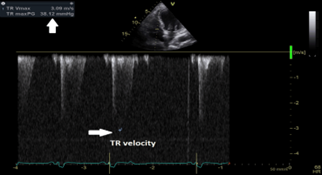

CW interpretation of the tricuspid regurgitant jet showed a decrease in TR velocity at 3.09 m/sec and thus an improvement of the SPAP at 43.1 mmHg with estimated RA pressure at 5 mmHg after correction of the hypocalcemia (figure 10).

Figure 10: Continuous wave doppler interpretation of the tricuspid valve showing a decrease of the tricuspid regurgitant velocity (white arrows) at 3.09 m/sec; with a subsequent decrease of systolic pulmonary artery pressure at 43.1 mmHg. TR velocity=Tricuspid regurgitation velocity

All cultures including blood cultures deep tracheal aspirate (DTA) cultures and urine cultures taken during this admission were negative. Patient’s HF medications were restarted in the few days that followed. He was also started on oral calcium and active vitamin D (1.25 hydroxy vitamin D); with monitoring of serum calcium level and a target of calcium level at around 8-8.4mg/dl, he was discharged home 3 weeks after presentation to ER. Before discharge from hospital (after 3 weeks) patient was in stable clinical condition not requiring oxygen therapy and was able to ambulate unassisted.